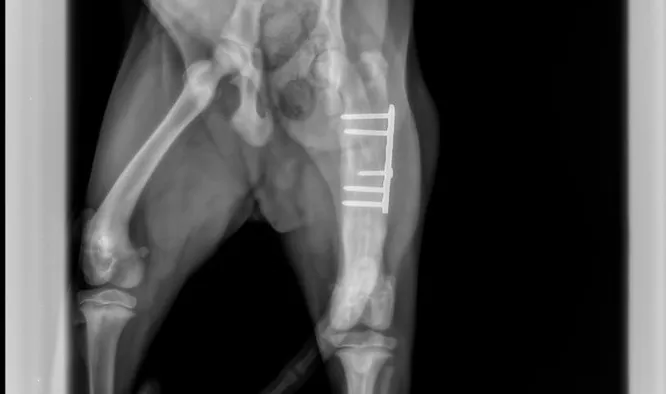

- Fracture repair (Plating, plate/rod, cross pin, compressive screw, etc.)

Fracture Repair Services

At Caring Hands, while our doctors are general surgeons and not board-certified orthopedists/surgeons, they are orthopedically trained by the AO organization which is a prestigious international orthopedic foundation that focuses on orthopedic care in both human and veterinary patients. We offer robust fracture repair options through the use of high-quality plating systems, rods, pins, wires, and screws. If you're worried that your furry loved one has broken his/her leg, our doctors will start by taking x-rays and then will develop a plan using special fracture planning software before operating. We will provide you an honest estimate, and provide you with several options of how to carry that plan out which in limited situations may include referral to specialists if its a case we don't feel comfortable operating on. We do take referrals from other hospitals that don't operate on bones! Give us a call and we will happy to serve you in anyway we can.

Caring Hands is proud to use very high quality human-quality orthopedic plating equipment (Movora/VOI) and orthopedic drills (Stryker)